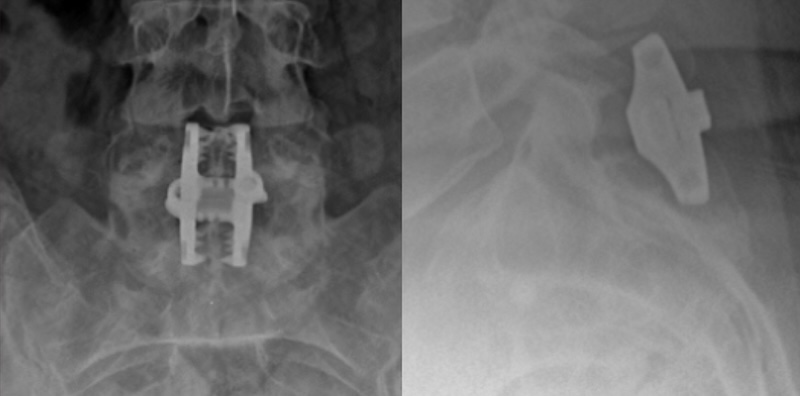

InSpan Interspinous Clamp Fixation

The Inspan Spinous Process Plate System by NANISX (Company of KIC Ventrures) is an interspinous process stabilization clamp composed of titanium with a contour that allows it to fit snugly up against the lamina. It features two interconnected plates that compress together against the spinous process to produce stabilization across the two vertebrae.